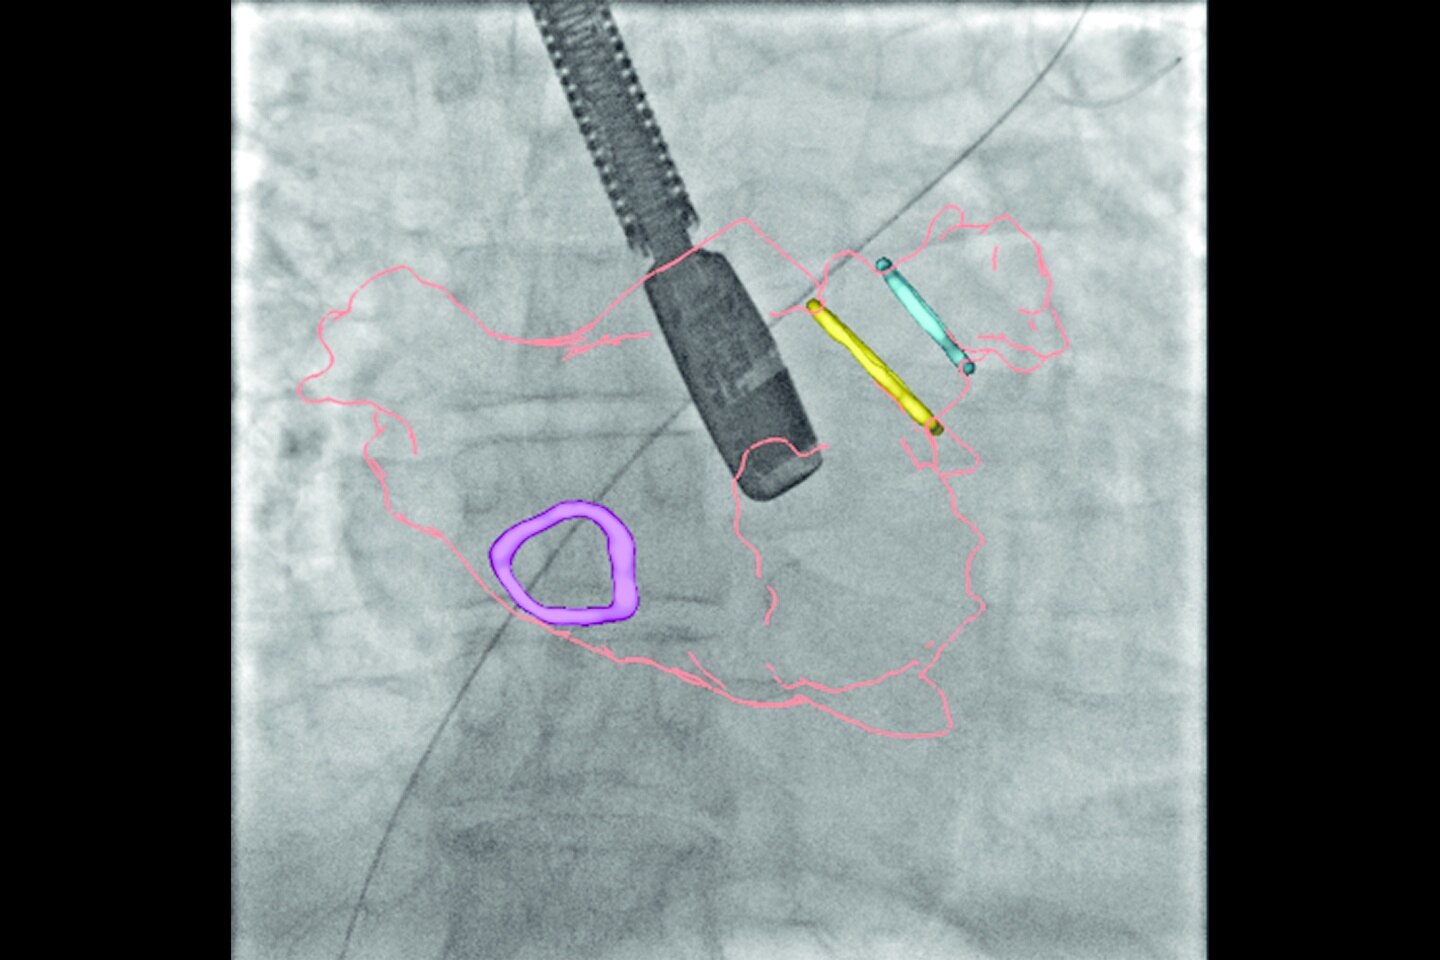

Un arco C 3D para todos los días: Desde fijación de columna o fracturas ortopédicas a angiograma y posicionamiento de stent.

Flexibilidad de imagenología realmente 3D y 2D. Pasando fácil y rápidamente entre ellas, proporcionando mayor eficiencia y versatilidad para una amplia gama de aplicaciones clínicas, desde columna y ortopedia hasta cardiología y vascular. Finalmente, un arco C 3D que todo equipo de cirugía merece.

Imagenología 2D premium desde cirugía general hasta cardiología intervencionista